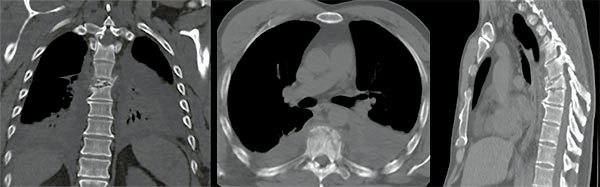

Figura 3:

Caso 24. A: Fractura L1: B1; N1. B: Control 7 meses que evidencia consolidación. C y D: Retiro de osteosíntesis a los 9 meses con buena movilidad en las radiografías dinámicas de control.

Figura 6:

Caso 8. A la semana de la primer cirugía el paciente se encontraba en condiciones y se realizó la corpectomía por via lateral MIS.

Figura 7:

Caso 8. Control postoperatorio alejado del paciente con un buen callo de fusión, sin pérdida de corrección.